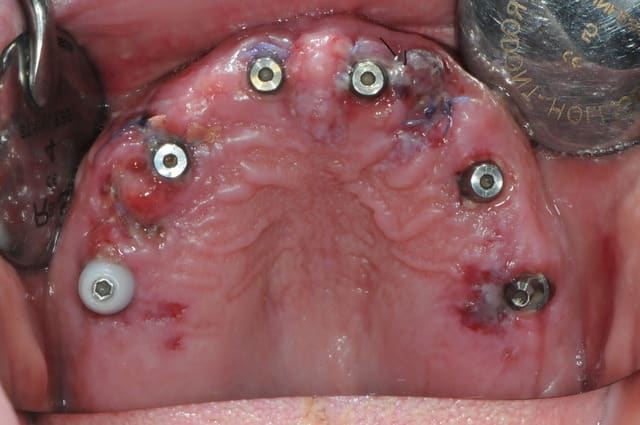

la patiente a été opérée hier et j'ai mis ses prothèses aujourd'hui.

la veille de l'intervention j'ai imprimé le model 3 D.

je vous mets les radios per-op.

secteur 1:

à l'aide du guide je détermine la position et l'axe de l'implant.

retrait du guide et contrôle radio puis pose des implants